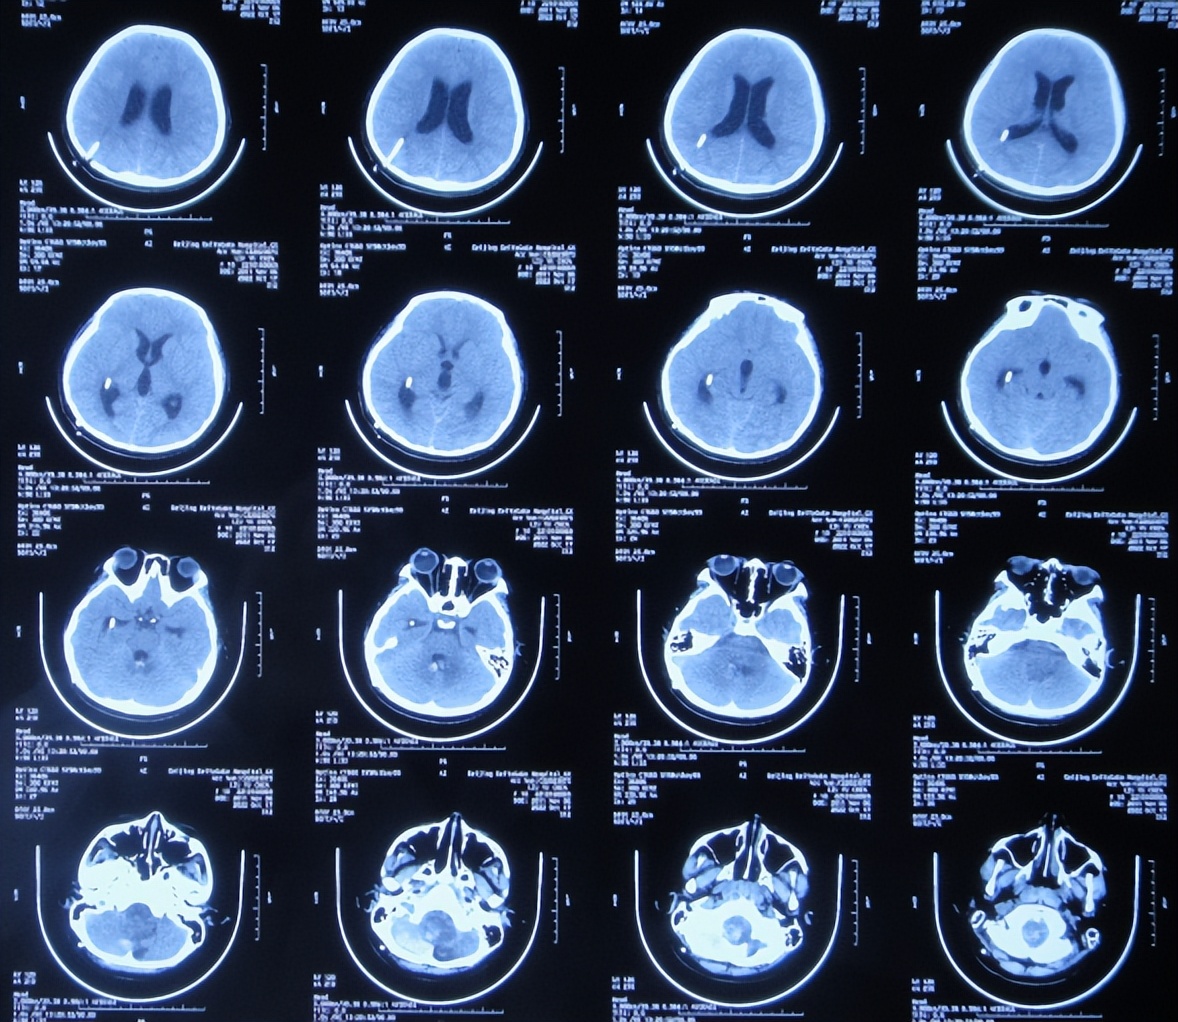

2022年10月16日(小脑出血当天晚上)住入李小勇脑脊液科。入院时:嗜睡,能被叫醒;时有恶心呕吐( 图-2 )。查头颅CT示小脑出血,脑室有扩张( 图-3 );肺部感染( 图-4 )。

图-3: 入院时颅脑CT晚上8点

图-5: 2022年10月17日术后颅脑CT

但脑室腹壁外引流术后2天即2022年10月19日,患儿症状并未明显减轻,查颅脑核磁示脑室有缩小( 图-8 ),计划明日进行脑瘤切除术。

2022年10月20日(住院治疗4天),进行了正中入路延髓占位切除术( 图-9 );术后不能拔除气管插管,转入重症监护病房。

2022年10月30日(住院治疗14天),头痛加重,查颅脑CT示脑室又有扩张( 图-12 );肺部感染( 图-13 )。

图-12: 2022年10月30日颅脑CT

2022年10月31日(住院治疗15天),进行了脑室腹壁外引流管调整术( 图-14 )。

图-14: 2022年10月31日颅脑CT

2022年12月12日(住院治疗57天),颅脑CT示脑室引流术后状态( 图-15 ),给予夹闭引流管。

图-15: 2022年12月12日颅脑CT

但夹闭5天后即2022年12月17日,患儿出现不适,查颅脑CT示脑室有扩张( 图-16 ),打开引流管。

图-16: 2022年12月17日颅脑CT

2022年12月20日(住院治疗65天),查头颅CT示脑室缩小( 图-17 ),肺部CT示感染好转( 图-18 )。

图-17: 2022年12月20日颅脑CT

2023年1月9日(住院治疗85天即脑胶质瘤切除术后81天)出院,出院时:意识清楚,头痛恶心完全消失,自己走路不稳( 图-19 );出院时肺部感染变好、颅脑CT示无异常( 图-20 )。

图-20: 出院时颅脑CT